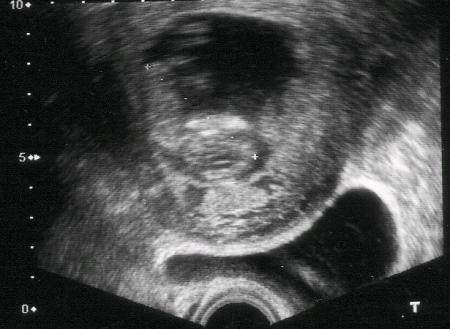

***AuJoUrD'HuI J'AiS vU béBé***

***Je SuIs a 12 sEmAiNeS***

***J'AiS vU cEs mIgNonE pEtiTeS mAiNs***

***Un pEtiT cLiChé PoUr VoUs***

***Il fAut éTrE tRéS AtEnTiF***

***AlOrS oN aRrIvE a VoIr BéBé***

***DiTE MoI sI vOuS l'AvEz Vu?***